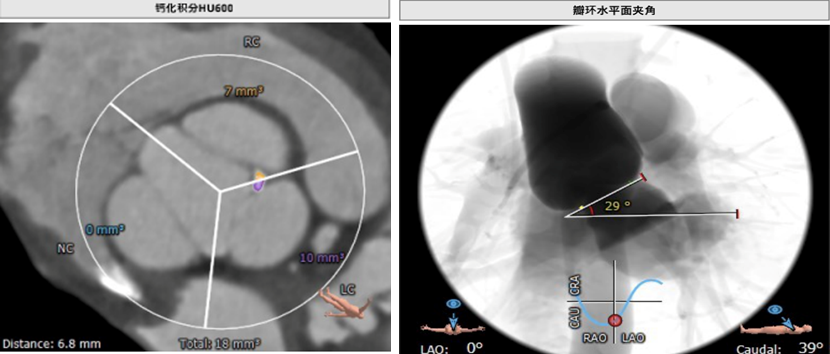

术前CT测量:

瓣环:27mm;LVOT:26.8mm;STJ:37.9mm;升主动脉:37.4mm;左冠高度:20.2mm;右冠高度:28.9mm;钙化积分:18mm3;瓣环与水平面夹角:29°;心尖入路夹角:108°。